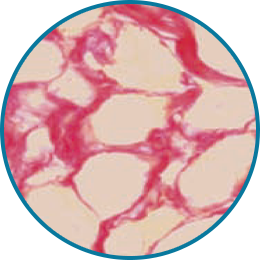

레디어스의 CaHA는 바이오 스티뮬레이터로

ECM 구성 성분 5가지를 만들어냅니다.

5가지 재생 성분은 약해진 피부 중심을 단단히 채워줍니다.

피부에 주입시켜 섬유아세포의 활성과 텐션을 회복하는 것은 바이오 스티뮬레이터인 레디어스의 가장 큰 특징입니다.

피부 탄력성, 두께감, 피부결 개선

조직회복, 콜라겐 1형의 구조적 지지

피부 탄력성, 피부 탄탐함

수분 보충, 피부 탄탄함

혈액 공급, 영양분 공급

시술 직후, 피부와 주변 조직이 건강하게 재생되기 시작하고 콜라겐을 비롯한 탄력 성분들이 자연스럽게 활성화되며 피부 세포의 기능이 점차 정상화됩니다.

이러한 과정을 통해 피부는 다시 탄력을 찾고, 시간의 흐름에 맞서 되돌리는 듯한 턴에이징 효과를 경험하게 됩니다.